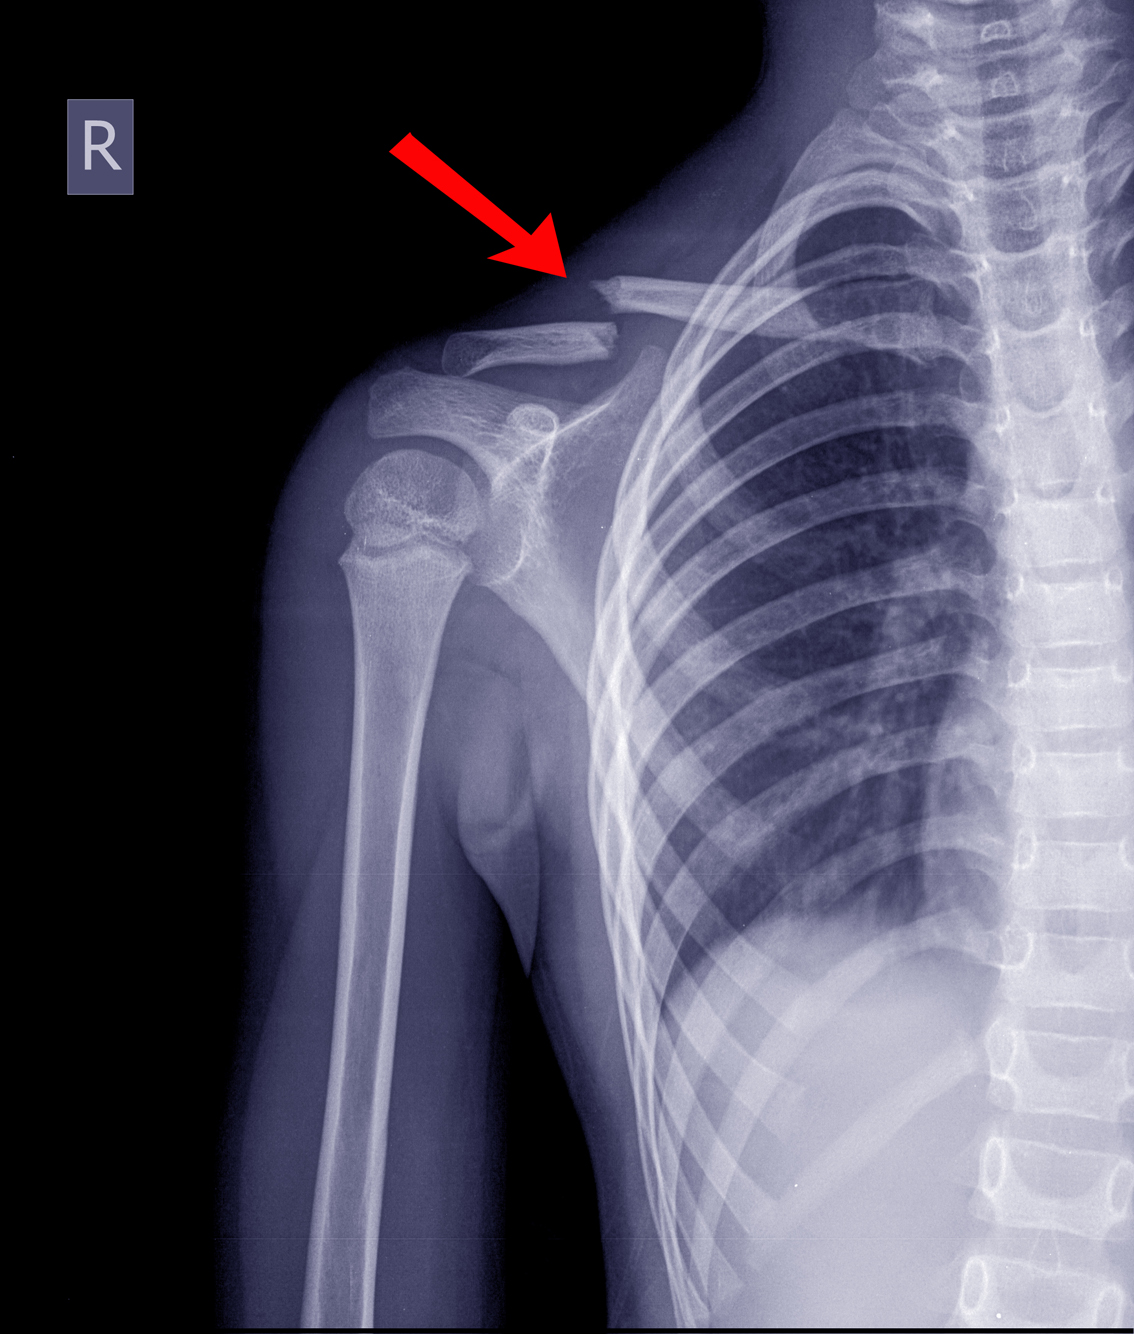

Normalmente, se usa como alternativa para los pacientes que padecieron luxaciones o están bajo tratamientos después de fracturas en la clavícula.

Además, en este estudio se expone que estas fracturas representan entre el 2.6% y el 10% del total. Por este motivo es importante aliviar los dolores de esta zona con inmovilizadores de clavícula.